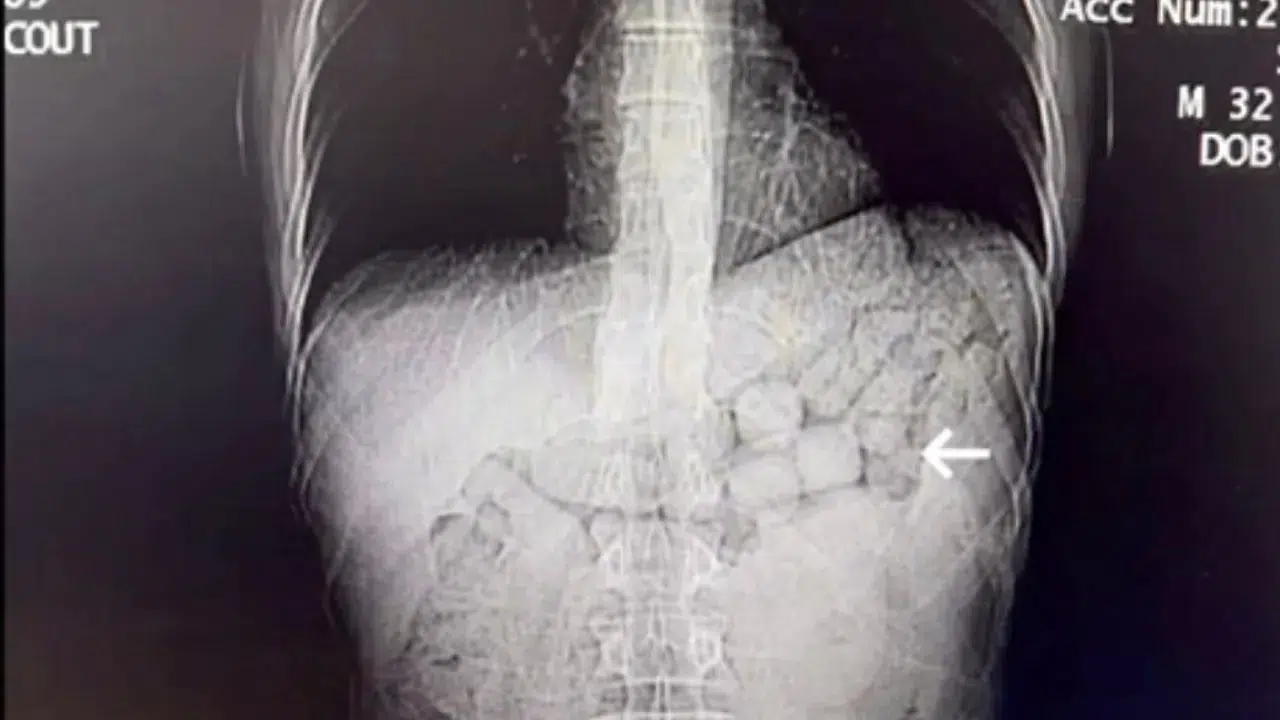

Fenerbahçe’nin Polonyalı futbolcusu Sebastian Szymanski, kasık bölgesindeki ağrı nedeniyle Corendon Alanyaspor karşılaşmasının kamp kadrosuna alınmadı.

Fenerbahçe’de Sebastian Szymanski, kasık bölgesinde yaşadığı ağrı nedeniyle Corendon Alanyaspor karşılaşmasının kamp kadrosunda yer almadı.Polonyalı futbolcunun tedbir amaçlı dinlendirildiği ve tedavi…